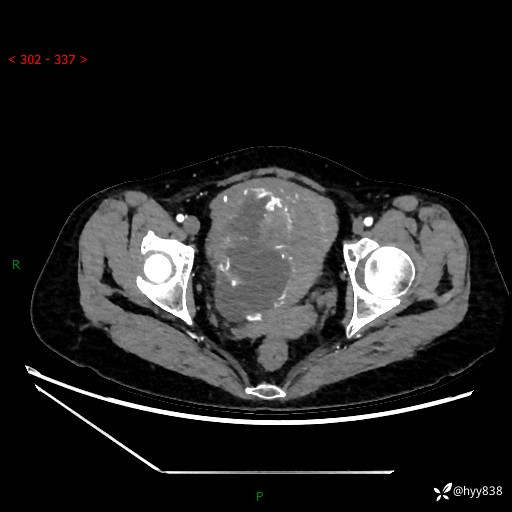

辅助检查:CT

盆腔CT平扫

增强(动脉期+静脉期)